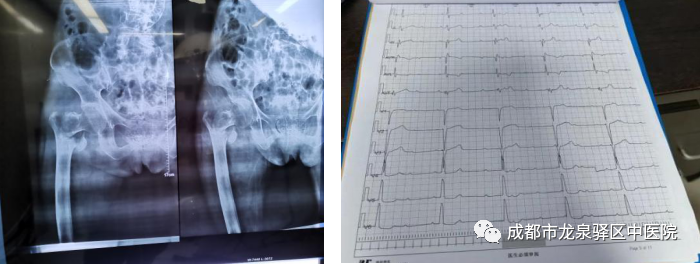

面对这种棘手情况,为确保手术安全,骨科主任请示院长后,立即联系我院医联体上级单位——成都中医药大学附属医院(简称附院)心内科专家张德来副主任医师(目前派驻我院担任业务副院长),同时邀请附院麻醉科屈强主任及我院心内科、麻醉科、ICU两院、多学科科主任会诊。大家共同分析患者病情,制定出合理的手术、麻醉、术后管理等方案,向院领导汇报,并征得患者家属同意后,于8月4日13:30将患者接进手术室。先在局麻下,由张德来副院长带领我院心内科张鹏主任为患者植入临时心脏起搏器;紧接着由屈强主任主导,我院麻醉科团队紧密配合,为患者行气管插管静脉全身麻醉,桡动脉穿刺置管监测动脉血压;随后由张成勇主任带领我院骨科团队为患者行股骨粗隆间骨折切开复位内固定手术。由于患者病情较重、体位改变等多种因素,患者心率、血压剧烈波动,整个手术过程异常惊险!心率最慢时22次/分,好在多科室有条不紊、紧密配合、通力协作,一切才有惊无险,顺利完成整台手术。术后患者转入重症医学科康复治疗,目前患者生命体征平稳,精神状态良好。